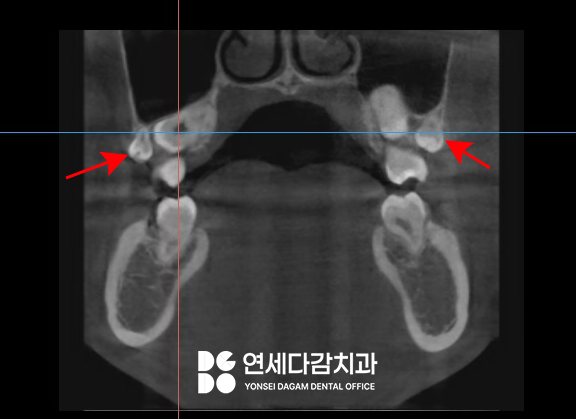

생각하는 부분은 위턱이었는데요.

상악 사랑니는 해부학적으로

상악동이라는 공기주머니 같은

구조물과 가까운 위치에 존재합니다.

상악동은 얇은 점막으로

둘러싸여 있는데,

제3대구치와 겹쳐 존재하게 되면

이를 빼는 과정에서

천공될 가능성이 있습니다.